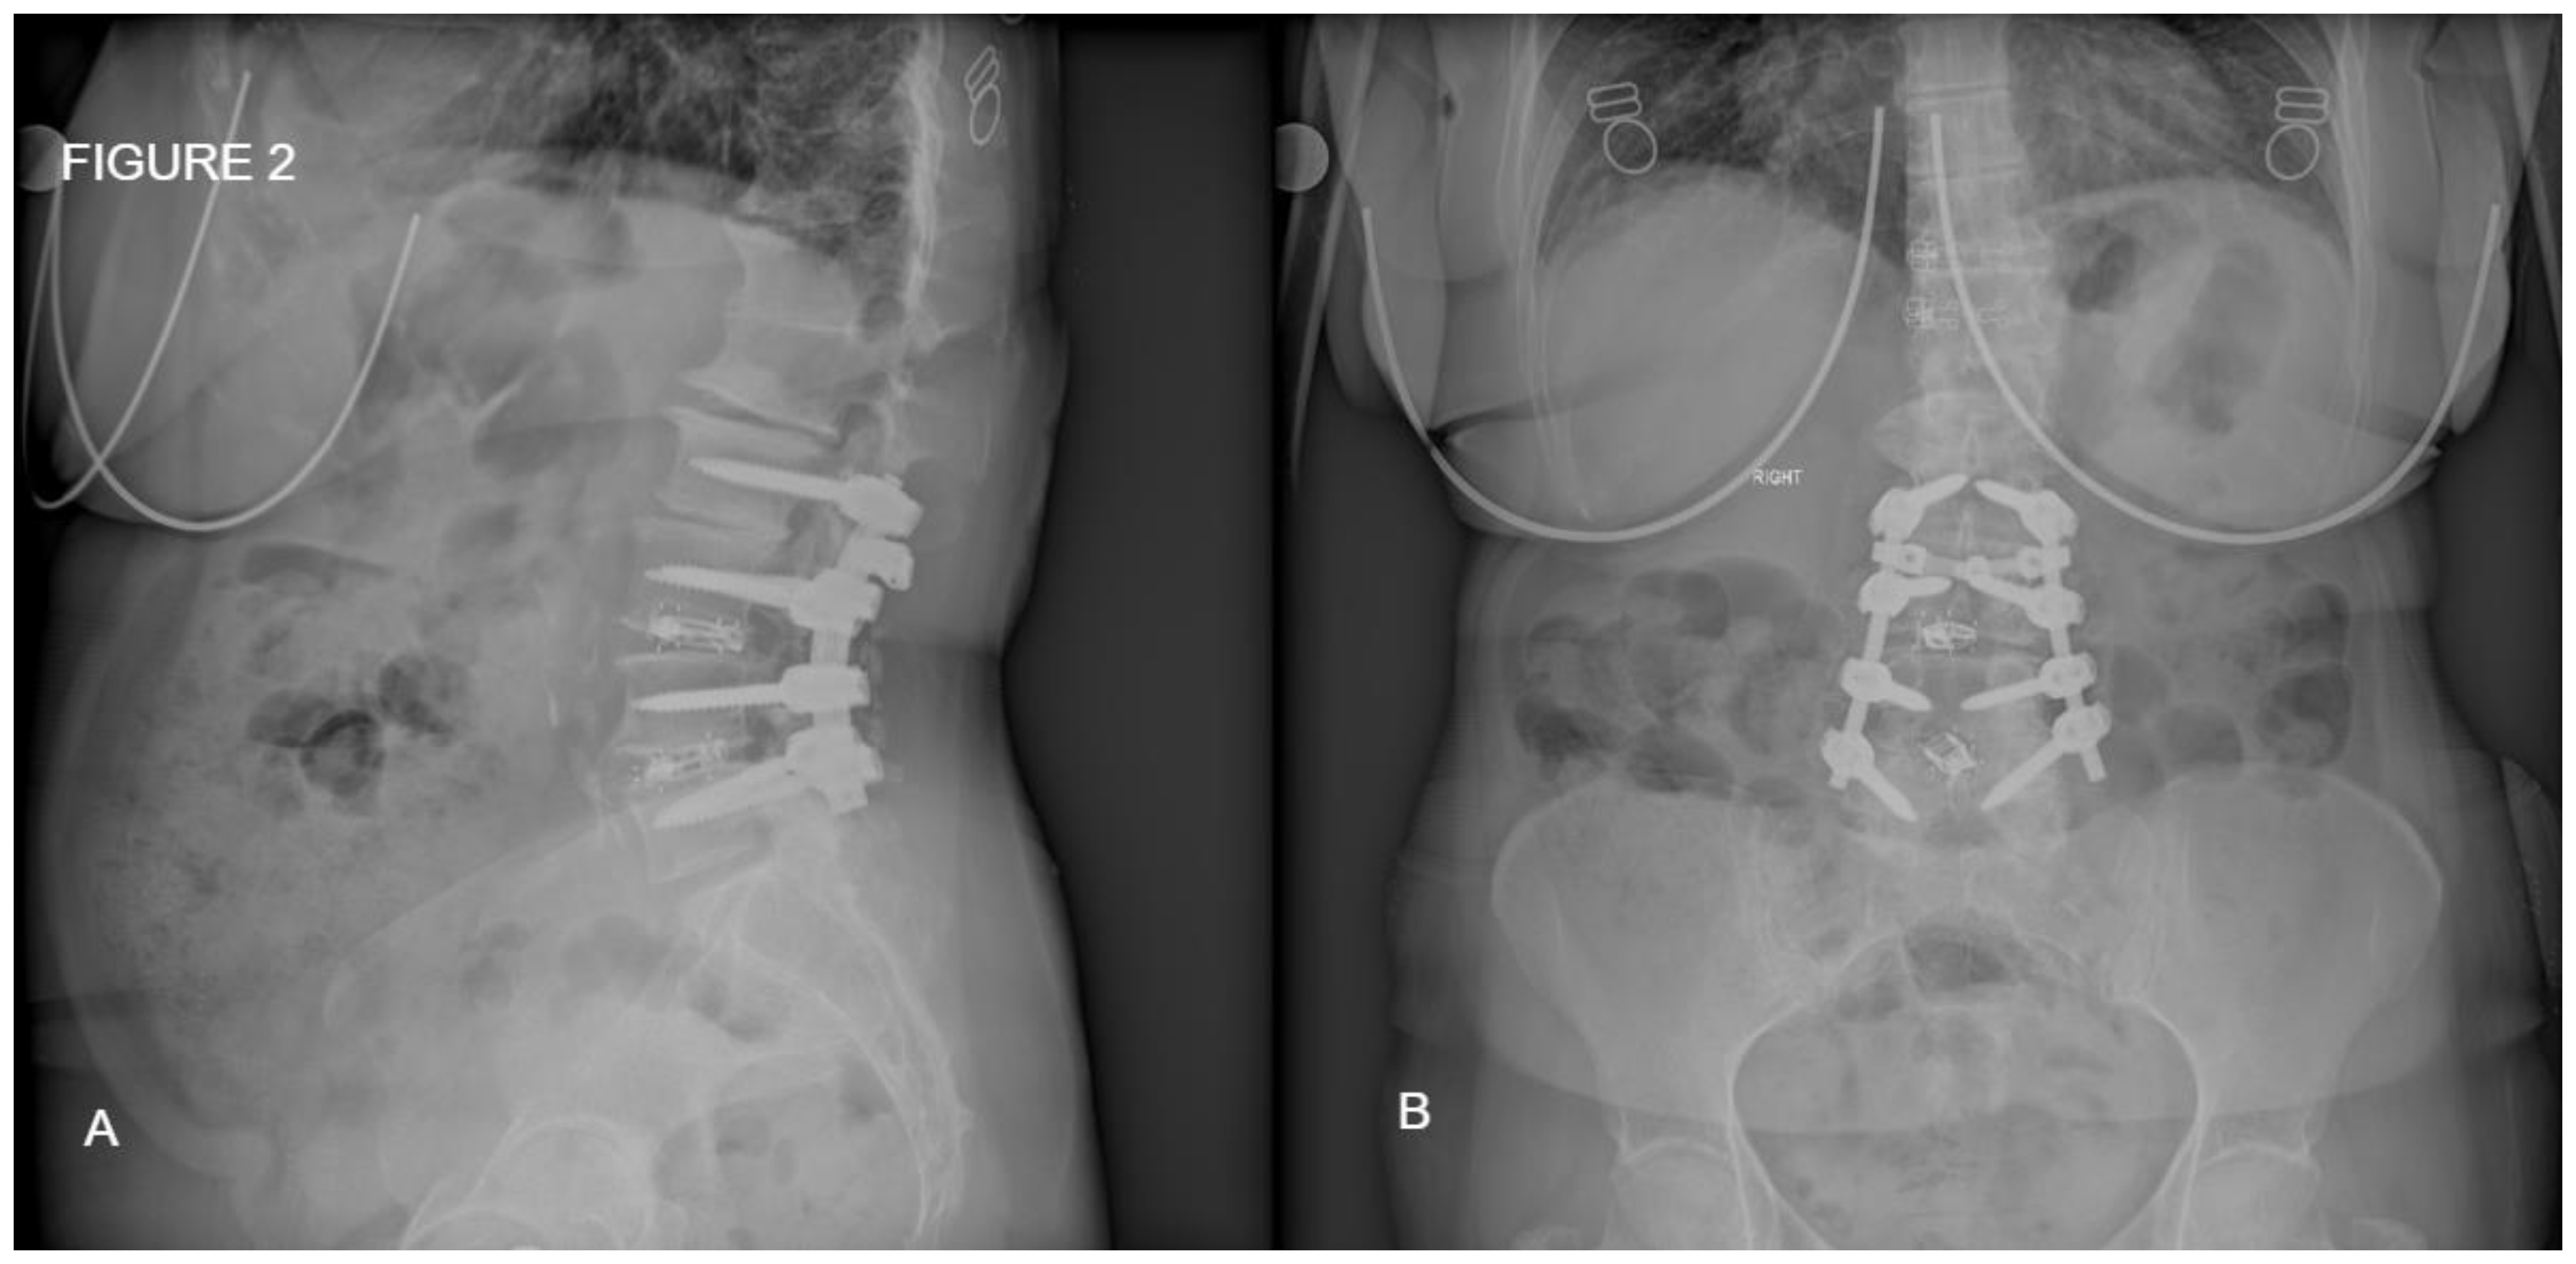

Figure 3. Postoperative CT scan of one level posterior fixation with interbody fusion after one year of follow up demonstrating satisfactory bone formation with bone union.